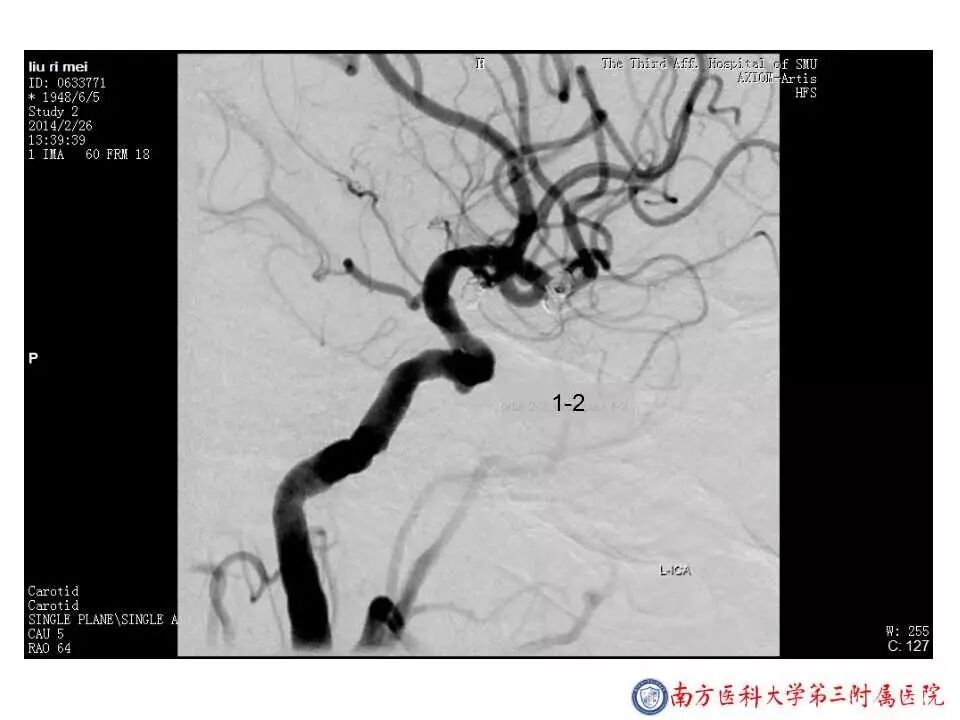

今天为大家分享的是“强生医疗CNV-神经介入专栏”第二十五期,由南方医科大学第三附属医院神经外科主任黄理金教授带来的“Enterprise支架辅助栓塞动脉瘤的优势”精彩讲课视频及PPT,欢迎观看。文章仅代表作者个人观点,如有不同见解,欢迎同道斧正!